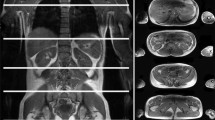

In our study, EI was increased in all FSHD muscles, while only 64% of them showed qualitative MRI changes (Mercuri 1–4). In particular, QMUS was able to identify muscle alterations also in the presence of mild or no MRI changes (Fig. 3), demonstrating a good sensitivity of QMUS, in agreement to what was reported in a previous study [29]. It has been highlighted the delay between histopathological abnormalities and the onset of muscle MRI alterations in some myopathies [32]; it could be hypothesized that, especially in superficial muscles where US has the best resolution, QMUS could identify the presence of fat replacement in advance with respect to MRI. Interestingly, QMUS showed significant increase of EI in deltoid muscle, which is generally spared in FSHD imaging. In our study, scanned muscles were chosen based on both the general knowledge of muscle involvement in FSHD [16] and the accessibility of the single muscles to US examination. Both the muscle selection that limited the study to five superficial muscles and the semi-quantitative nature of the analysis of T1-weighted MRI images may have influenced the different sensitivity of QMUS vs. MRI. However, this is an important point because, while the availability and applicability of muscle MRI is limited in many centres, muscle US is a fast and immediate technique which, simply by setting a specific program on a common US machine, makes it possible to collect quantitative measurements and to provide important clinical and diagnostic information.

Muscle MRI and US matching. A Images of right and left tibialis anterior, appearing normal on MRI (Mercuri scale 0) (yellow arrows) and on US (yellow arrowheads). B Images of right and left tibialis anterior, completely fat replaced at MRI (Mercuri scale 4) (yellow arrows), and the corresponding US image that shows increased echogenicity and structural tissue changes (yellow arrowheads). C Images of right and left pectoralis major, appearing normal on MRI (Mercuri scale 0) (yellow arrows), while the right US image shows increased echogenicity and the left US image shows normal muscle echogenicity. D Images of right and left pectoralis major, appearing fat replaced at MRI (right: Mercuri scale 3, left: Mercuri scale 2) (yellow arrows), and the corresponding US image that shows increased echogenicity and structural tissue changes, more pronounced in the right muscle (yellow arrowheads)

QMUS and MRI data in the single muscles showed that the most T1-replaced muscles were the most hyperechoic (Fig. 3). However, we were unable to find any correlation between STIR hyperintensity and muscle echogenicity. STIR hyperintense muscles usually mean the presence of edema [33], which should make muscle appear hypoechoic on US. However, we observed that all muscles with STIR hyperintensity showed also T1 alterations and increased EI, pointing out a limit of US technique: muscle edema and fat replacement can coexist, and in this case, their distinction is possible with MRI, but not with US.